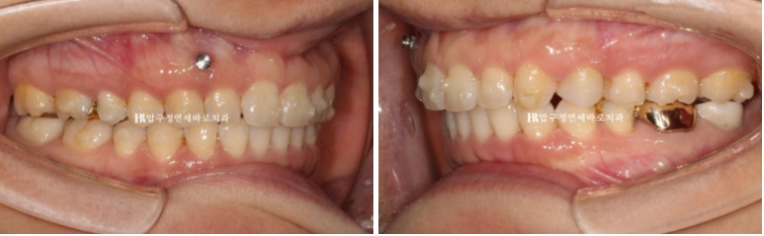

임플란트가 있어 치아이동이 제한된 좌측 교합이 역시 아쉽습니다.

임플란트로 인해서 중심선을 완전히 맞출 수 없지만 좀 더 개선을 위해서 추가장치 제작에 들어갔습니다.

24년 8월부터 12월까지 4개월간 추가장치를 더 꼈습니다.

중심선 개선을 위해 우측에 고무줄도 추가가 되었습니다.

그리고 12월에 드디어 11개월만 치료가 마무리가 되었습니다.

치축, 교합평면, 과개교합 모든 것이 정상이고 중심선은 여전히 조금 아쉽습니다.

임플란트 때문에 어금니 이동이 제한된 상황에서는 최선이겠지만요.